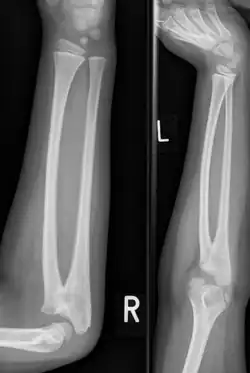

Eine Radioulnare Synostose (lat. Synostosis radioulnaris) bedeutet eine knöcherne Verbindung zwischen Radius (Speiche) und Ulna (Elle) knapp unterhalb des Ellenbogengelenkes. Eine Umwendbewegung ist dadurch nicht möglich.[1][2]

Ein Röntgenbild bestätigt die Diagnose aufgrund der typischen Fehlstellung des proximalen Radius, nicht abgrenzbarem Radiuskopf und Nachweis der Synostosierung.